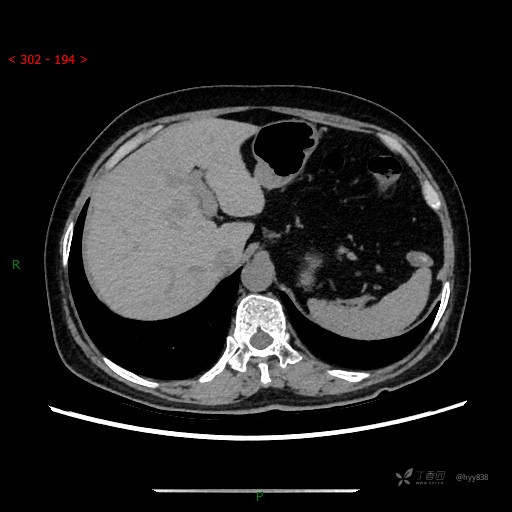

上腹部CT平扫